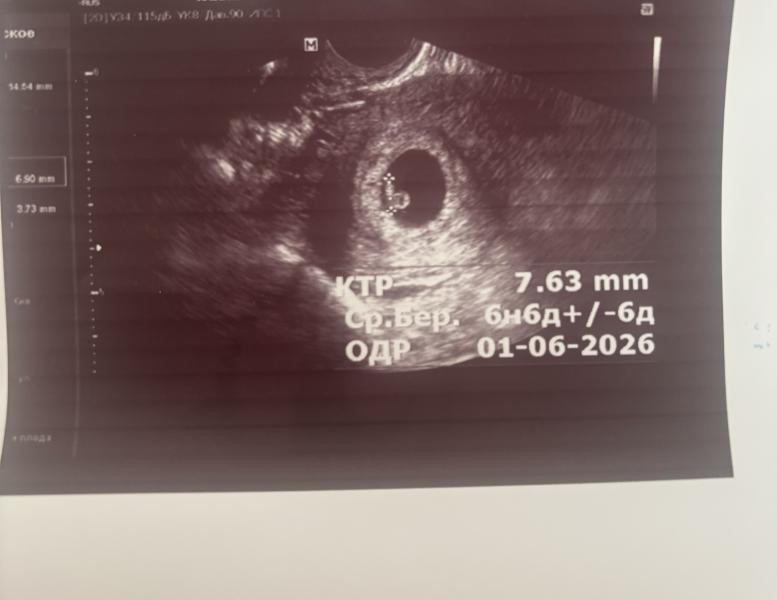

Второе узи

Человечек растет, сердечко услышали 💕

Такая горошинка🥹